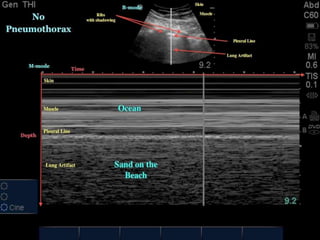

U/S in pneumothorax

• Ultrasound found to be more sensitive than CXR in

diagnosis of pneumothorax.

U/S signs of

pneumothorax

• Loss of lung sliding.

• Loss of comet tails.

• loss of seashore sign (M mode).

• Stratosphere sign or bar code sign(M mode).